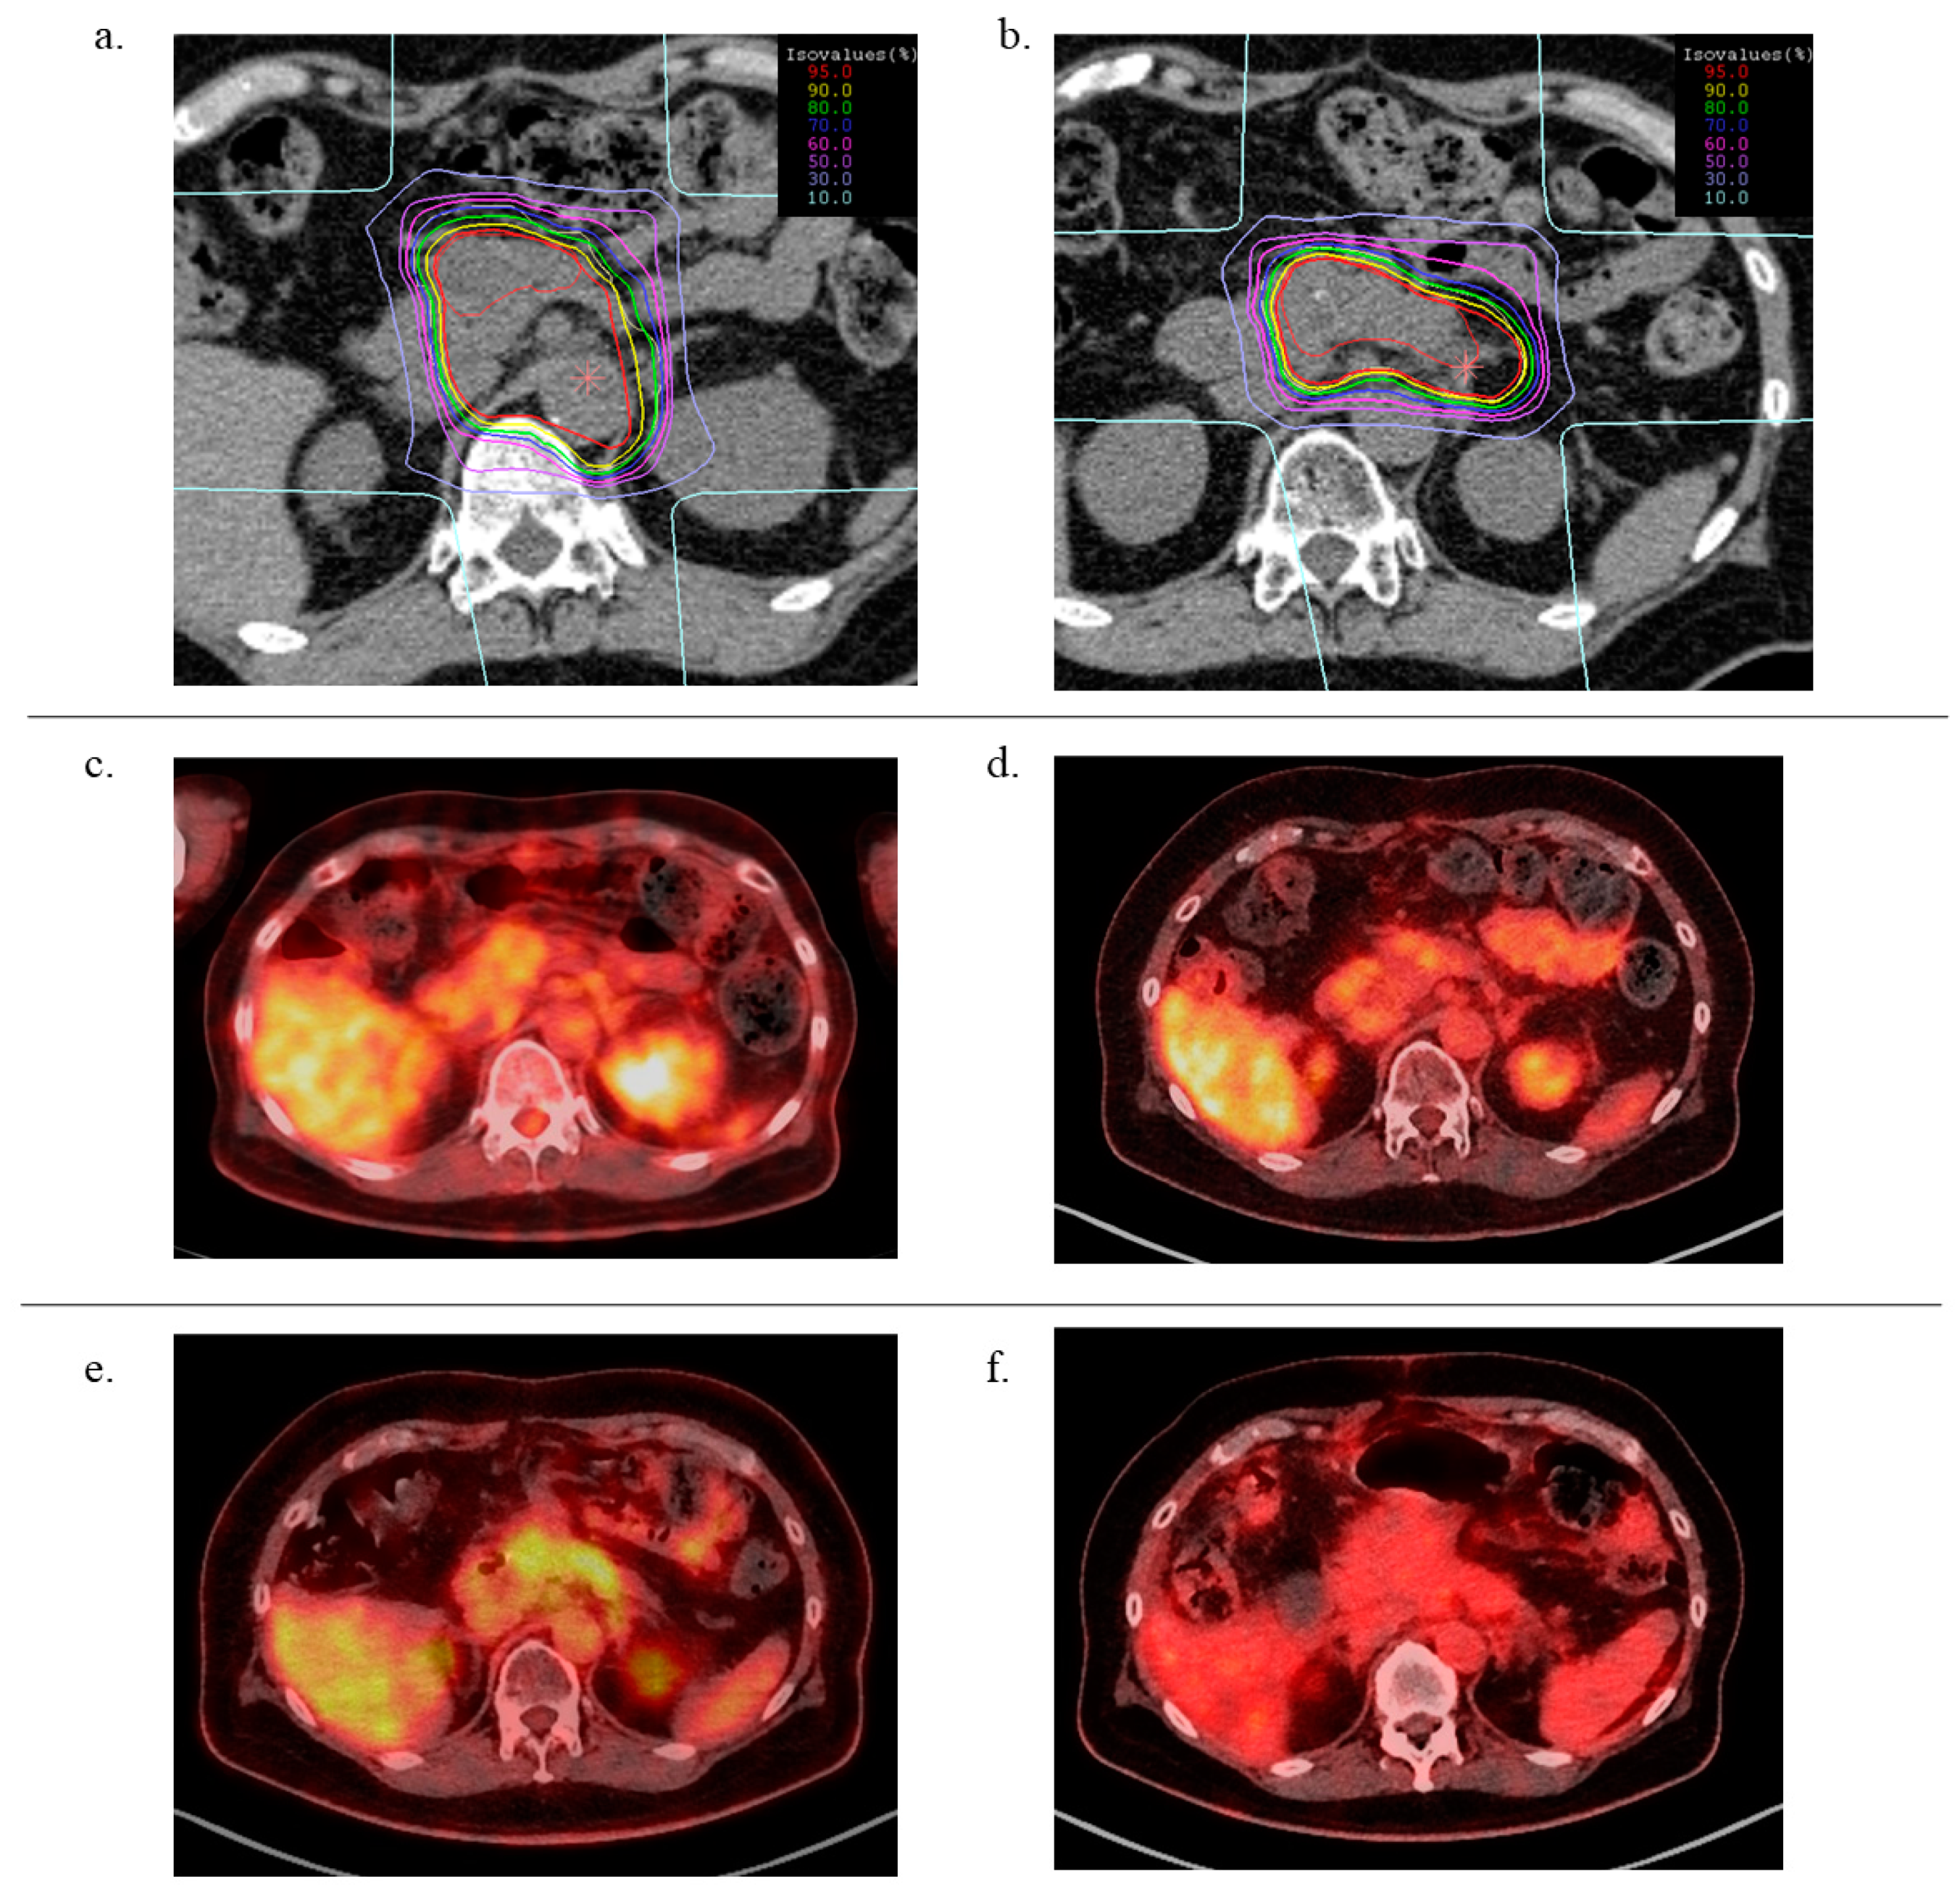

4.2. Carbon Ion Radiotherapy

4.3. Treatment Planning

4.4. Evaluation and Follow-Up